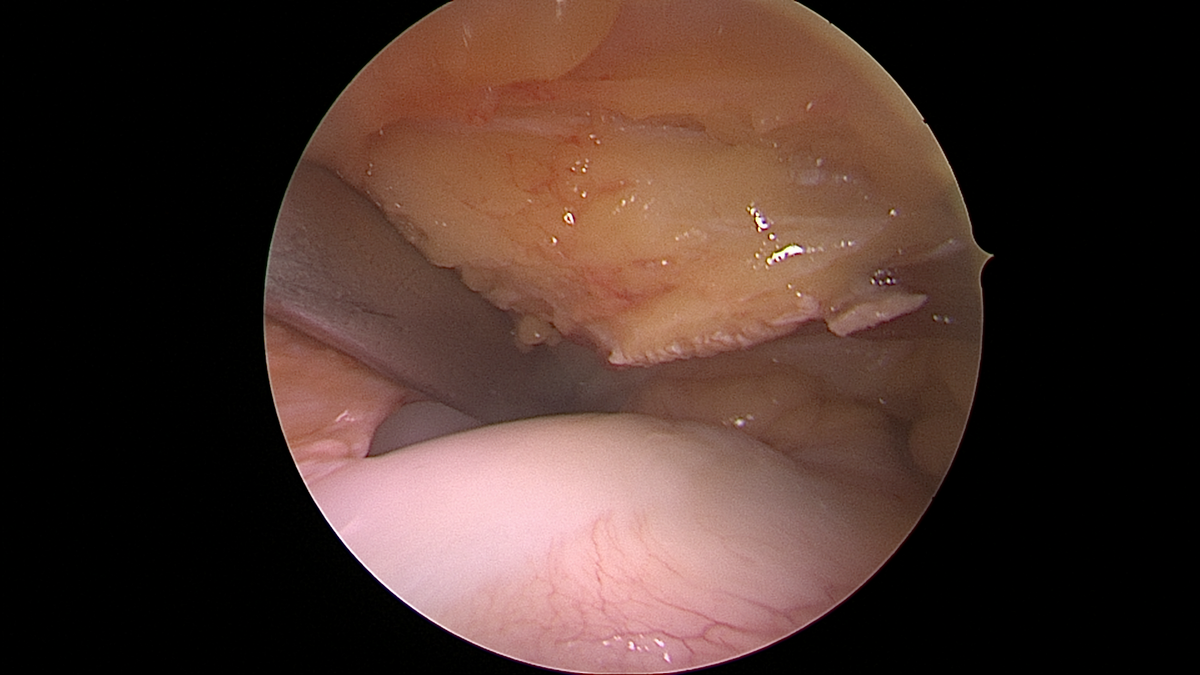

Knorpelschäden

Bei Knorpelschäden unterscheiden wir zwischen degenerativen Veränderungen („Arthrose“) und traumatischen Knorpelschäden. Je nach Größe, Lokalisation und Ursache für die Knorpelschäden wird eine individuelle Therapie abgestimmt. Konservative Therapiemöglichkeiten (Physiotherapie, Infiltrationen, Orthesen, …) sind ebenso eine Möglichkeit, wie die operative Behandlung.

Es ist wichtig, die Ursache für einen Knorpelschaden herauszufinden und ggf. mitzubehandeln. Neben einem Unfall ist auch eine chronische Instabilität oder eine Achsfehlstellung unter Umständen für einen Knorpelschaden verantwortlich – vor einer Knorpelreparatur ist die Behandlung der Ursache essenziell.

Als Behandlungsmöglichkeiten für Knorpelschäden gibt es die sog. Abrasionschondroplastik / Mikrofrakturierung, bei der der defekte Knorpel bis auf den Knochen abgetragen und dieser dann mit kleinen Löchern perforiert und ggf. mit einer speziellen Membran bedeckt wird. Durch die Perforationen tritt Knochenmark in den Defekt ein und es bildet sich ein sog. Regeneratknorpel. Auch die Möglichkeit einer Knorpelzelltransplantation (sog. „ACT“) wird bei uns angeboten. Hier werden in einer ersten Operation Knorpelzellen entnommen und in einer zweiten Operation in den Defekt eingebracht (entweder als sog. ACT Inject in einer Suspension oder als ACT 3d auf einer Membran). Auch die körpereigene Transplantation eines Knochen-Knorpel-Zylinders (OATS / Mosaikplastik) ist eine Therapiemöglichkeit, die wir anbieten können.